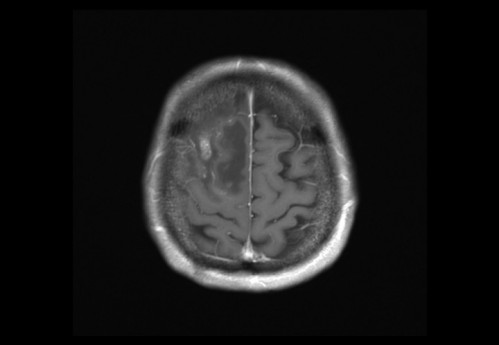

Sie behandeln einen 48-jähriger Mann, von Beruf Architekt. In der Anamnese erfahren Sie, dass er leidenschaftlich Gitarre spiele und er berichtet, dass ihm seit zwei Wochen in der rechten Hand die nötige Koordination fehle. Auch das Plektrum würde ihm immer wieder aus den Fingern gleitet.

Eine Magnet-Resonanz-Tomografie (MRT) des Kopfes wurde durch den ambulant behandelnden Neurologen bereits veranlasst.